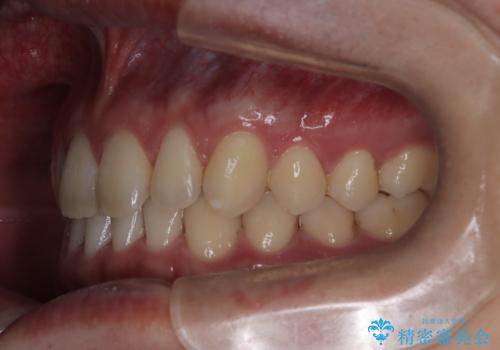

【インビザライン】前歯の隙間を治したい。

- 前歯の隙間を主訴に来院されました。

インビザラインにて治療しました。

ディープバイトも改善でき患者さんも満足されていました。

前歯の隙間だけを閉じる治療を行うだけでは、噛み合わせが悪くなるためディープバイトも改善が必要です。